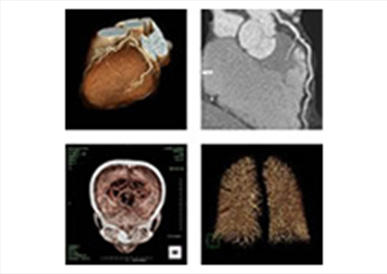

キャノン製80 列マルチスライスCT(Aquilion PRIME)

今回導入された CT 装置は新技術により低線量での撮影が可能で患者様にやさしい装置です。検査はとても簡単で広範囲の撮影が短時間で行え、頭部・胸部(心臓)・腹部(大腸)疾患にいたるまで、全身の診断が可能です。また、大口径の大型寝台は今まで懸念されがちな圧迫感を感じる事なく患者様はリラックスしながら安心して検査をお受けいただけます。

大腸CT検査について

- 内視鏡を使わない新しい検査です

- マルチスライスCT装置により3次元画像を作成して正確な検査が行えます

- 内視鏡挿入や造影剤注入の必要がないため苦痛の少ない検査です(吸収・排出されやすい炭酸ガスの注入は必要となります)

- 検査部屋入室から退室 まで20分程度の検査です

冠動脈CT(冠A-CT)検査について

当院では、冠動脈CT(冠A-CT)検査を行っております。

冠A-CT検査は、心臓の血管(冠動脈)をCTで詳しく調べる検査で、カテーテル検査の前段階として行える、体への負担が比較的少ない検査です。

冠動脈の狭窄(血管の狭くなり)や動脈硬化の状態を画像で確認することができ、自覚症状が出る前の早期の狭心症の発見や、将来の心筋梗塞のリスク評価(予知)に役立ちます。

胸痛・動悸・息切れなどの症状がある方はもちろん、 高血圧・糖尿病・脂質異常症がある方、健康診断で心疾患を指摘された方にも有用な検査です。

画像検査

X線CT装置で心臓を画像化するという試みは以前からありましたが、検査のためには息止め時間が最短でも40秒と非常に長く、患者さんに大きな負担を与えてきました。導入されているCT装置は、世界で初めて心臓の検査(120mmのスキャン範囲)を8秒の息止め時間で可能にした装置ですので患者さんの負担を大幅に軽減することが可能です。また立体像(3次元画像)として撮影部を360度自由な方向から観察することが可能です。

このX線CTを使用することにより、従来の画像診断装置では困難であった無症状の心血管の狭窄(きょうさく:せまくなっている)を早期に発見したり、カテーテル治療(細い管を体内に挿入し、その先端を風船状に膨らませて心血管の狭窄部分を広げたりする治療)のフォローアップ検査装置として期待されています。